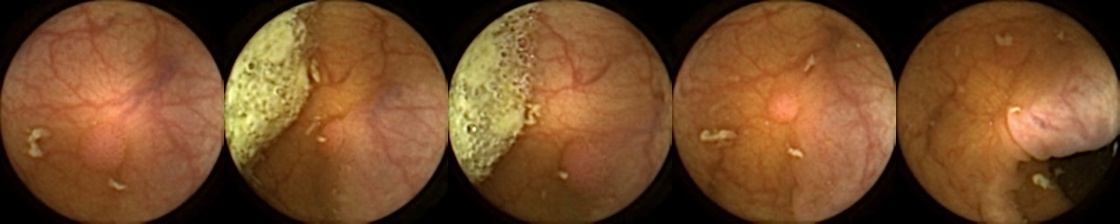

Refer to caption

Figure 1: Positive exemplar images with each row showing five images of a unique polyp, where in each row, the first image corresponds to first partial and fifth image is the last full view of the same polyp. The polyps have been marked in green for each image.

For MIV, we construct both positive and negative exemplar pairs from this multi-patient polyp image dataset. Positive exemplars are constructed based on the five images from a single polyp, with one of the second, third, or fourth image designated as the query and the remaining four images forming the target bag. Images from five example polyps are shown in Figure 1. Negative exemplars are constructed using a more sophisticated strategy: if a patient has multiple polyps, the query image is selected from one of those polyps at random, while target images are sampled from other polyps of the same patient; if a patient has only one polyp, target images are drawn from different patients entirely.